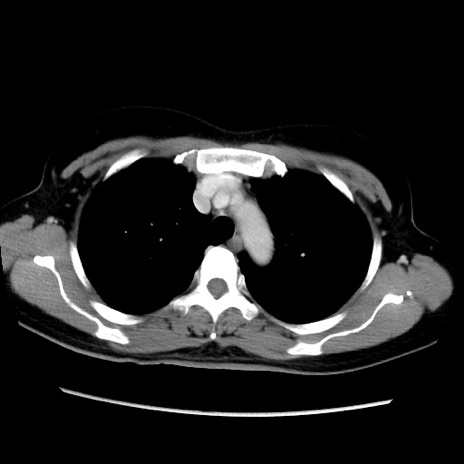

MRI(4日後)

【症例】40歳代女性

【主訴】上下腹部痛

【現病歴】2日目から下腹部痛あり。夜間は痛みで眠れなかった。昨日より上腹部痛と下痢が出現。臥位で痛みは軽快したため、休んでいた。本日になって臥位でも立位でも痛みが強くなってきたため救急要請。

【既往歴】子宮内膜症

【身体所見】部:平坦・軟、左上下腹部に圧痛あり、反跳痛あり。

【データ】WBC 21800、CRP 26.78